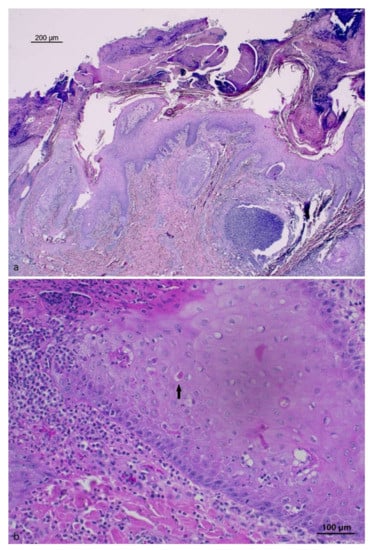

3.2. Histopathology